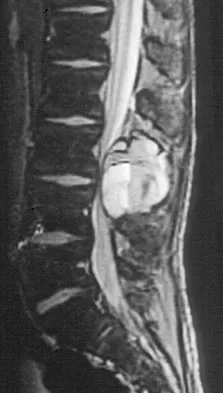

A 44-year-old woman has had lower extremity dysesthesias, urinary incontinence, and has been unable to walk for the past 2 days. She reports no pain or history of trauma. She notes that 3 weeks ago she missed work for 2 days because of back pain, but it resolved with rest. Examination shows decreased or absent sensation below the knees, no motor function below the knees, and decreased rectal tone. Catheterization results in a postvoid residual of 2,000 mL. Plain radiographs and MRI scans without contrast are shown in Figures 1a through 1d. What is the next most appropriate step in management?

Explanation

The patient has had a clear and sudden onset of a profound neurologic deficit. The radiographic studies suggest a lesion in the conus medullaris that appears to be intradural and intramedullary. MRI, with and without contrast, will best evaluate this mass further. The addition of gadolinium allows further evaluation of vascularity and the extent of the lesion. Eichler ME, Dacey RG: Intramedullary spinal cord tumors, in Bridwell KH, Dewald RL (eds): The Textbook of Spine Surgery, ed 2. Philadelphia, PA, Lippincott-Raven, 1997, vol 2, pp 2089-2116.